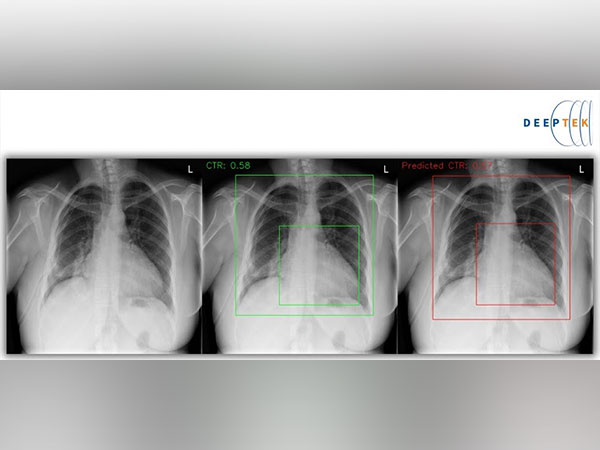

Enlarged Heart, Pulmonary Edema and Fluid in the Pleural Space Could Indicate signs of an underlying Heart Issue, can be screened by DeepTek's Path Breaking Innovative Machine Learning Technique for Digital Chest X-rays